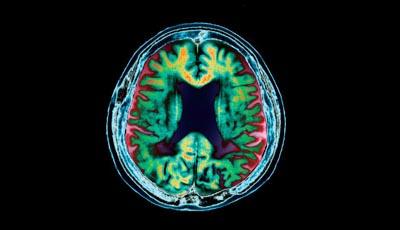

تبدیلی خون سے بھی الزائمر کا خطرہ

لندن.... حافظے کی کمزوری اور ذہنی یکسوئی کے فقدان کا سبب بننے والی مشہور زمانہ الزائمر بیماری کی مختلف وجوہ سامنے آچکی ہیں مگر سائنسدانوں نے اپنی تازہ تحقیقی رپورٹ میں کہا ہے کہ الزائمر کے مریض کی دماغی صلاحیت کم ہوتی ہے اور حافظہ ذخیرہ کرنے والے دماغی گوشہ کی بالائی رنگت کبھی سرد اور کبھی پیلی نظرآتی ہے اوریہی وہ عمل ہے جو دماغی صلاحیت کو کمزورکرتا ہے تاہم ڈاکٹر کچھ مریضوں کو تبدیلی خون کا مشورہ دیتے ہیں جو کسی حد تک کارگر بھی ہوتا ہے مگر تازہ ترین تحقیق سے پتہ چلتا ہے کہ خون کی تبدیلی بھی از خود الزائمر کا سبب بن سکتی ہے اسلئے جس مریض کو بھی کسی دوسرے کا خون دیا جائے اس میں حد سے زیادہ احتیاط برتنی چاہئے اور خون دینے سے قبل مریض اور اس شخص کا ٹیسٹ لینا ضروری ہے جسکا خون اس مریض کودیا جارہا ہو۔50سال قبل الزائمر کو ہارمون کی نشوونما میں خلل کا نتیجہ بھی سمجھا جاتا تھا۔